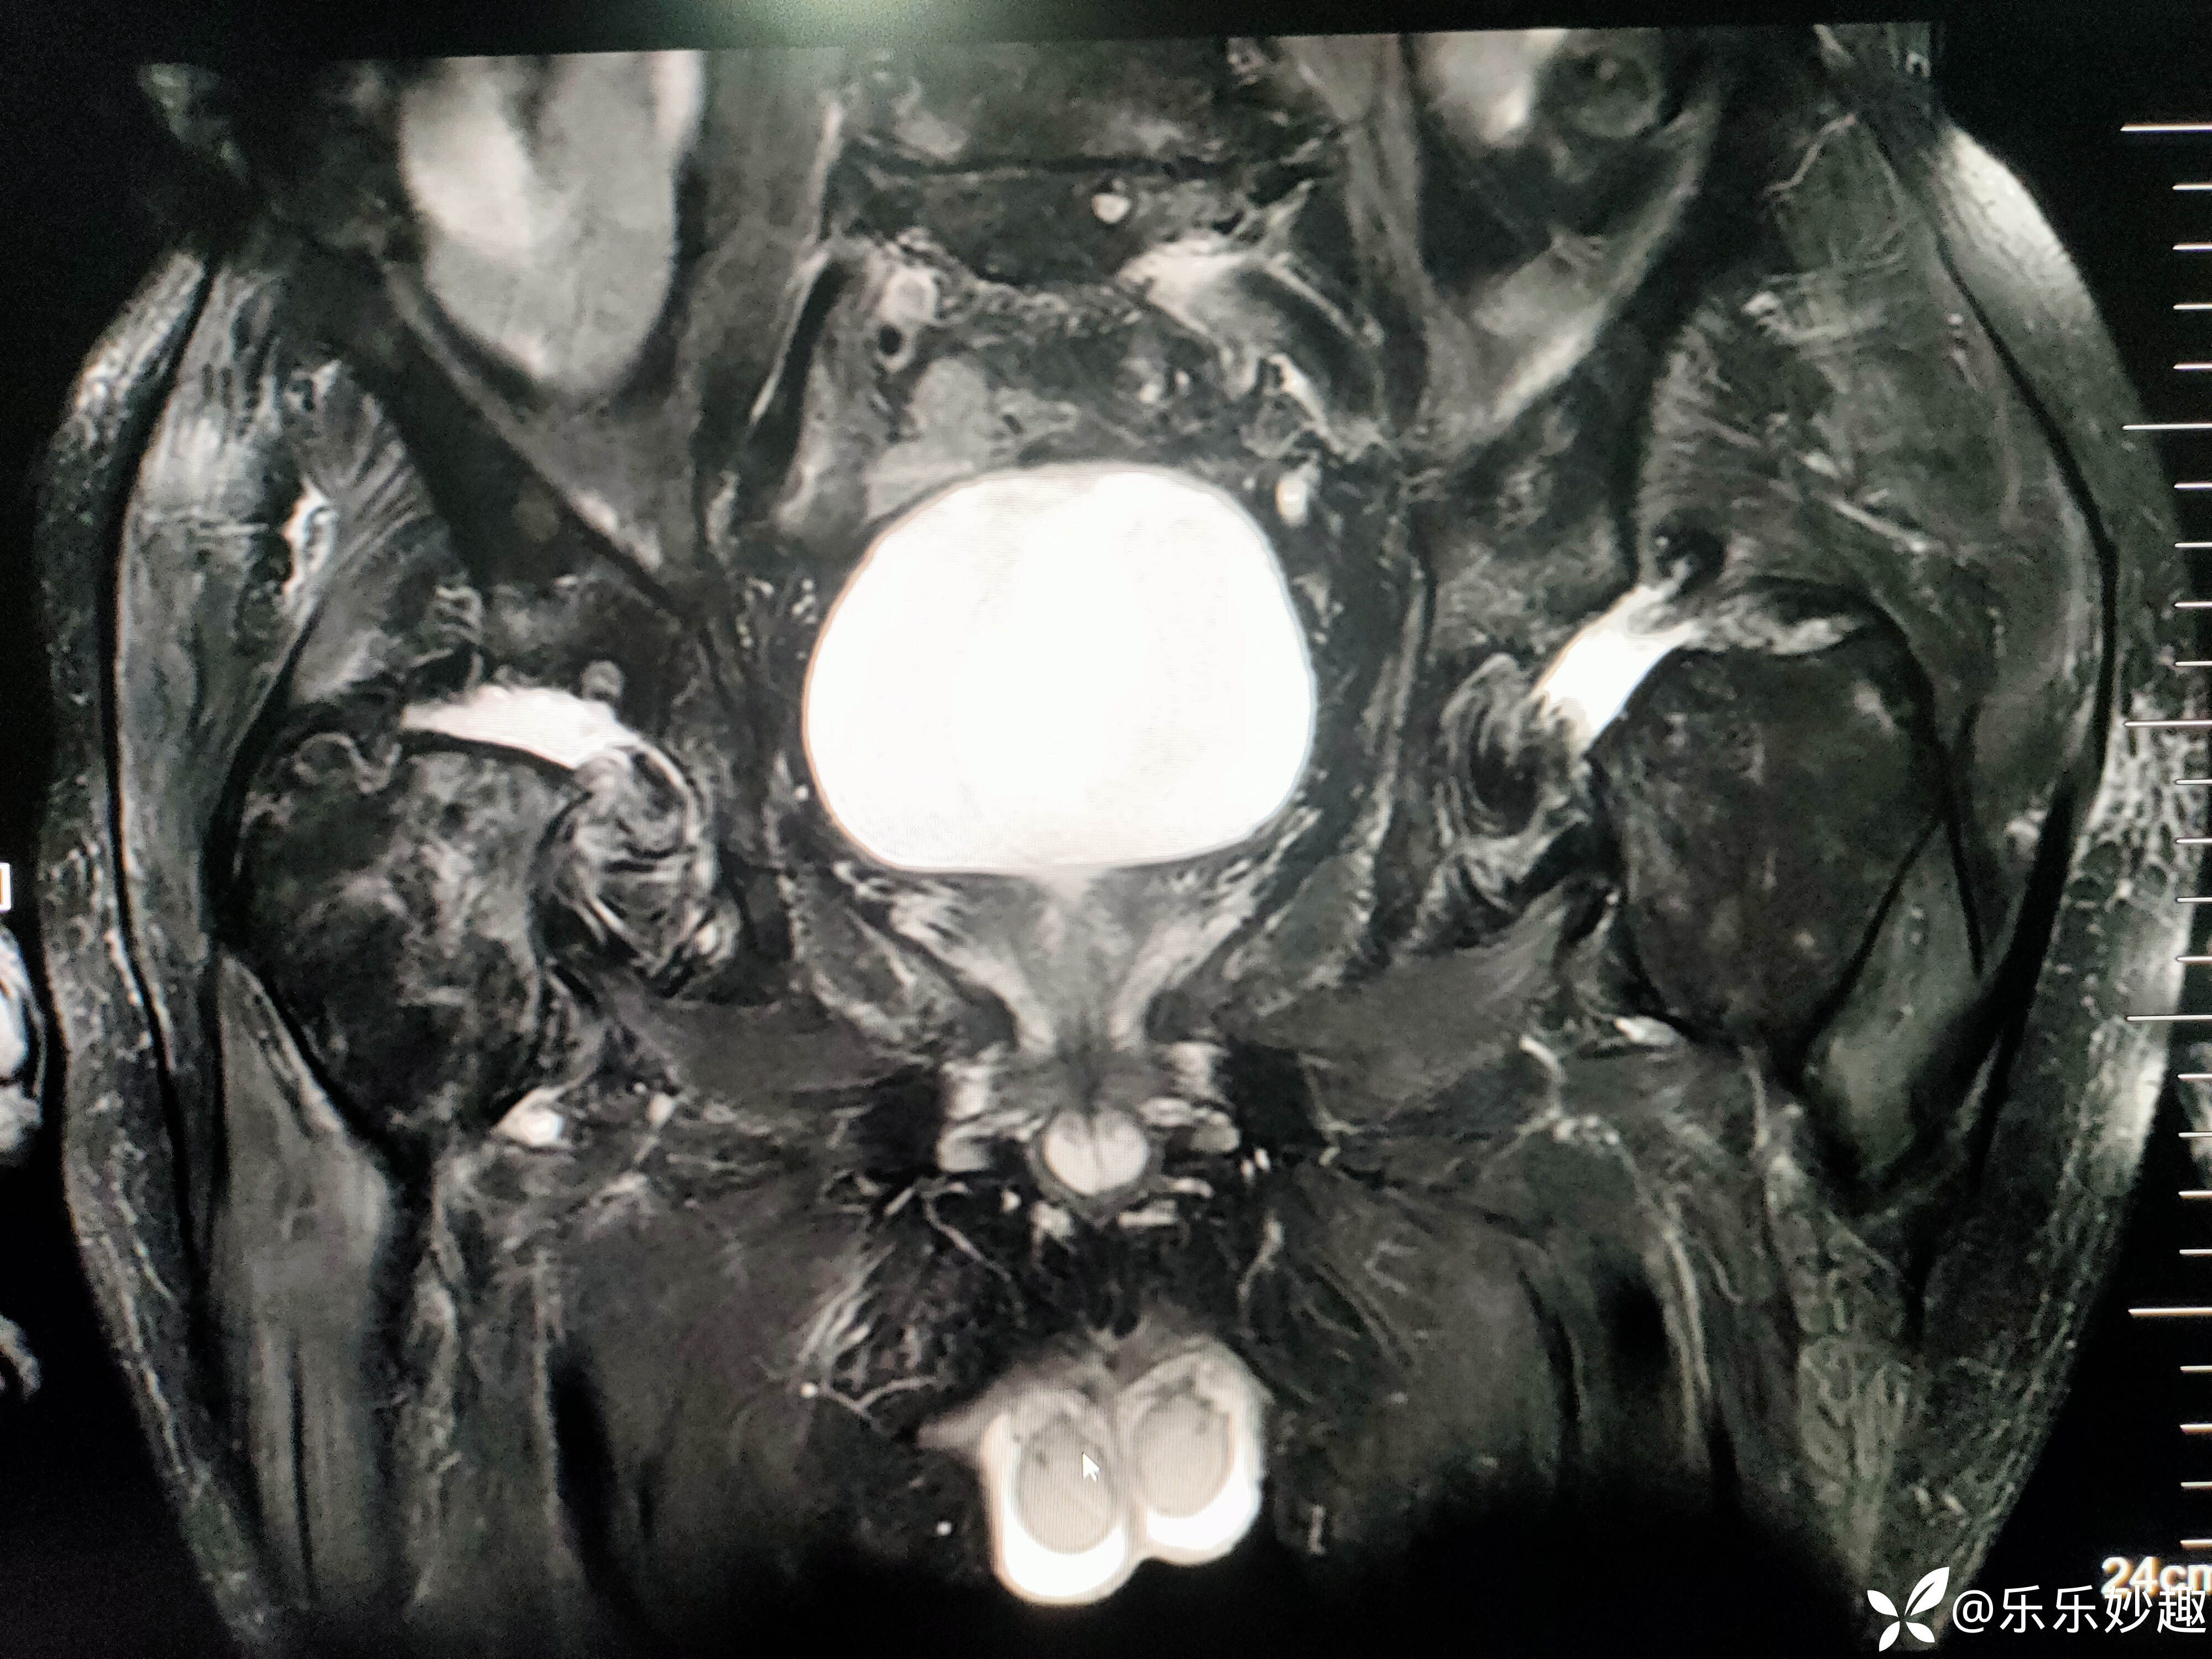

最后做了髋关节MR,见下图